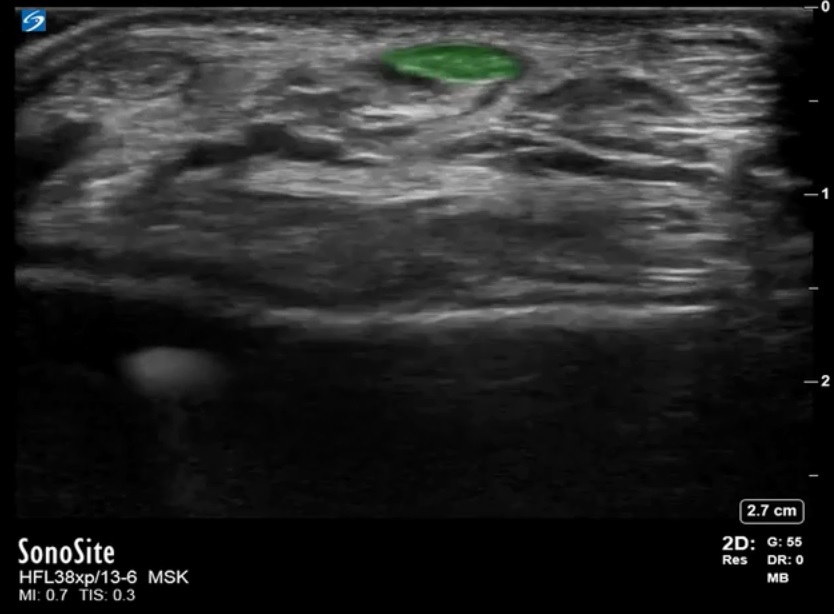

Bild: Fuß und Sprunggelenk, Recessus anterior des Extensor hallucis longus

Markierter Bereich: Sehne des Extensor hallucis longus